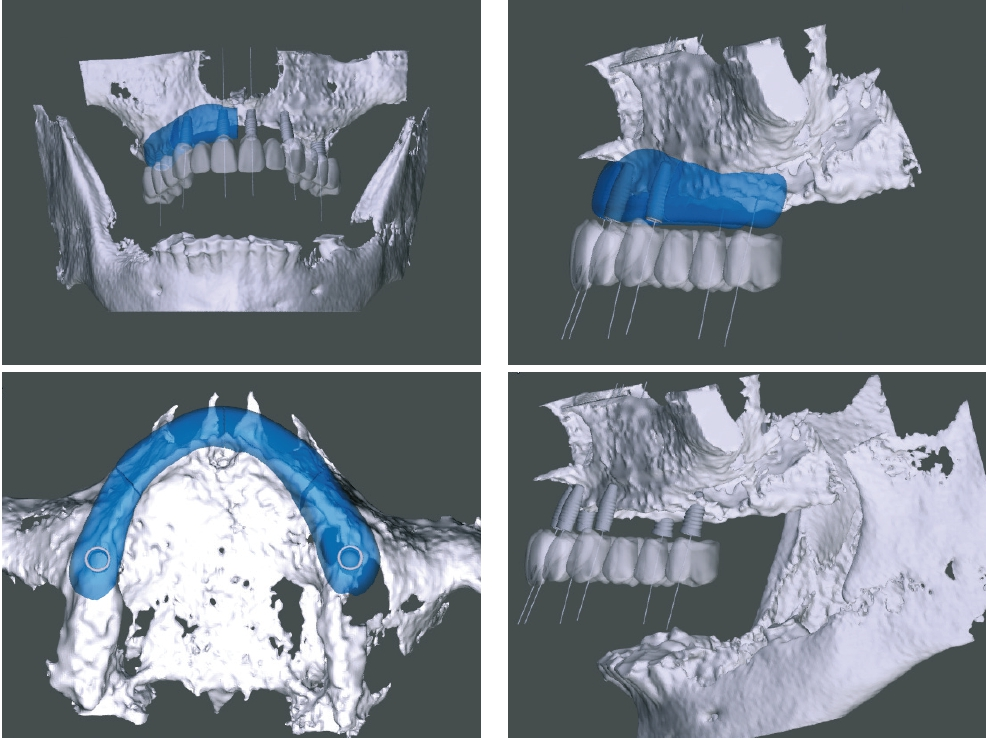

Die Transplantate werden, basierend auf einem dreidimensionalen Bild (CT/DVT), in der CAD-Software konstruiert und mittels CAM-Frästechnologie nach hohen Qualitätsstandards hergestellt. Die so gefertigten Knochenblöcke werden vom Autor seit mehr als zehn Jahren verwendet. Der maxgraft bonebuilder (Botiss, Berlin) ermöglicht u. a. komplexe horizontale und vertikale Augmentationen, ohne den Patienten durch Entnahme von Eigenknochen zu belasten. Zudem kann eine maximale Kontaktfläche mit dem ortsständigen Knochen erreicht werden. Da eine manuelle Anpassung während des chirurgischen Eingriffs wegfällt, verkürzt sich die Operationszeit deutlich. Diese signifikant reduzierte Operationszeit, die Schmerzreduktion und die zu erwartende verbesserte Wundheilung sprachen auch im vorliegenden Fall für diese Option.

Aufgrund der hochgradigen Atrophie des Kieferknochens war für die geplante implantatprothetische Versorgung eine absolute Kieferkammerhöhung notwendig. Nach gründlicher Anamnese und Patientenaufklärung begann die Behandlung.

Erweitertes Backward Planning